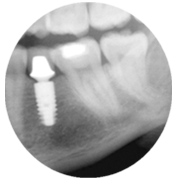

The unique friction-lock and keyed TissueCare connection creates such a close fit between the two components that subcrestal implant placement is possible. This leads to a positive bone response, enabling the desired emergence profile and transgingival healing.

In other words, Ankylos offers the versatility of a twopiece system while maintaining healthy hard and soft tissue and keeping it free from irritation.